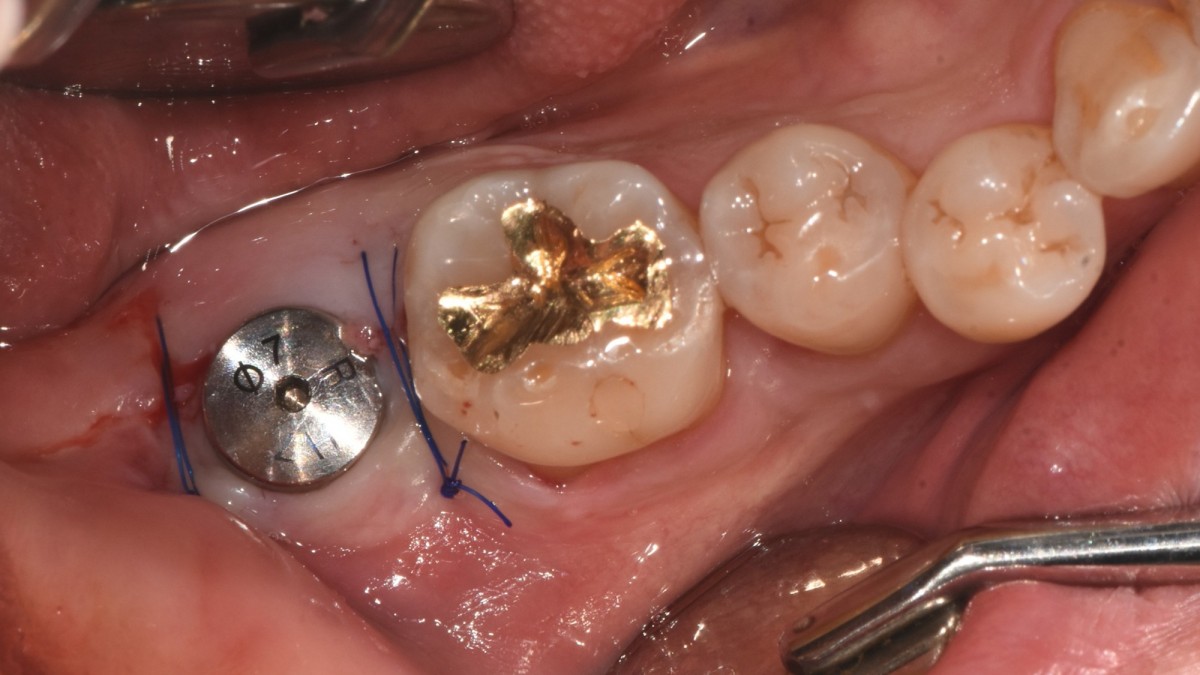

A 47-year-old male patient had a crown with an ill-fitting margin and crack-tooth syndrome in the lower 2nd molar. No systemic issue.

▲extraction